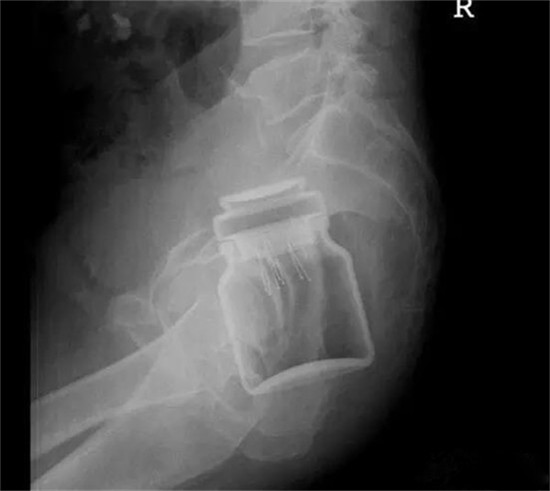

这个是什么瓶子?

这也是一个玻璃瓶。也需要麻醉下取出来。

塞进直肠的灯泡。这个是女性病人。

塞进直肠的灯泡。

灯泡大头先塞进去,自己根本就取不出来。

也是一个白炽灯灯泡,是小头先塞进去。看出来男女了吗?

这也是一个白炽灯灯泡,是小头先塞进去老外灯泡的说明书上,有不要把灯泡塞进嘴巴的说明,说塞进去自己取不出来。

这是一个直径8厘米的玻璃圆球。

直肠里塞了灯泡或者圆球,是肛门自慰人群的常见意外。

要取出灯泡,需要肛门充分松驰,才能取出来。可以在肛门处打局麻,但是效果不好,不够松,可以打腰麻或者硬麻,当然,最好是全麻,就可以有满意的肛门松驰。

上面图片是产钳,从直肠里把直径8厘米的圆球拽出来。

只要产钳能够夹住灯泡或者圆球,把肛门扩大,可以轻松把灯泡拽出来。不用担心灯泡会碎了。当然,为了保险起见,可以在直肠与肛门处打 润滑油如石蜡油,有润滑后,会更容易拽出来。